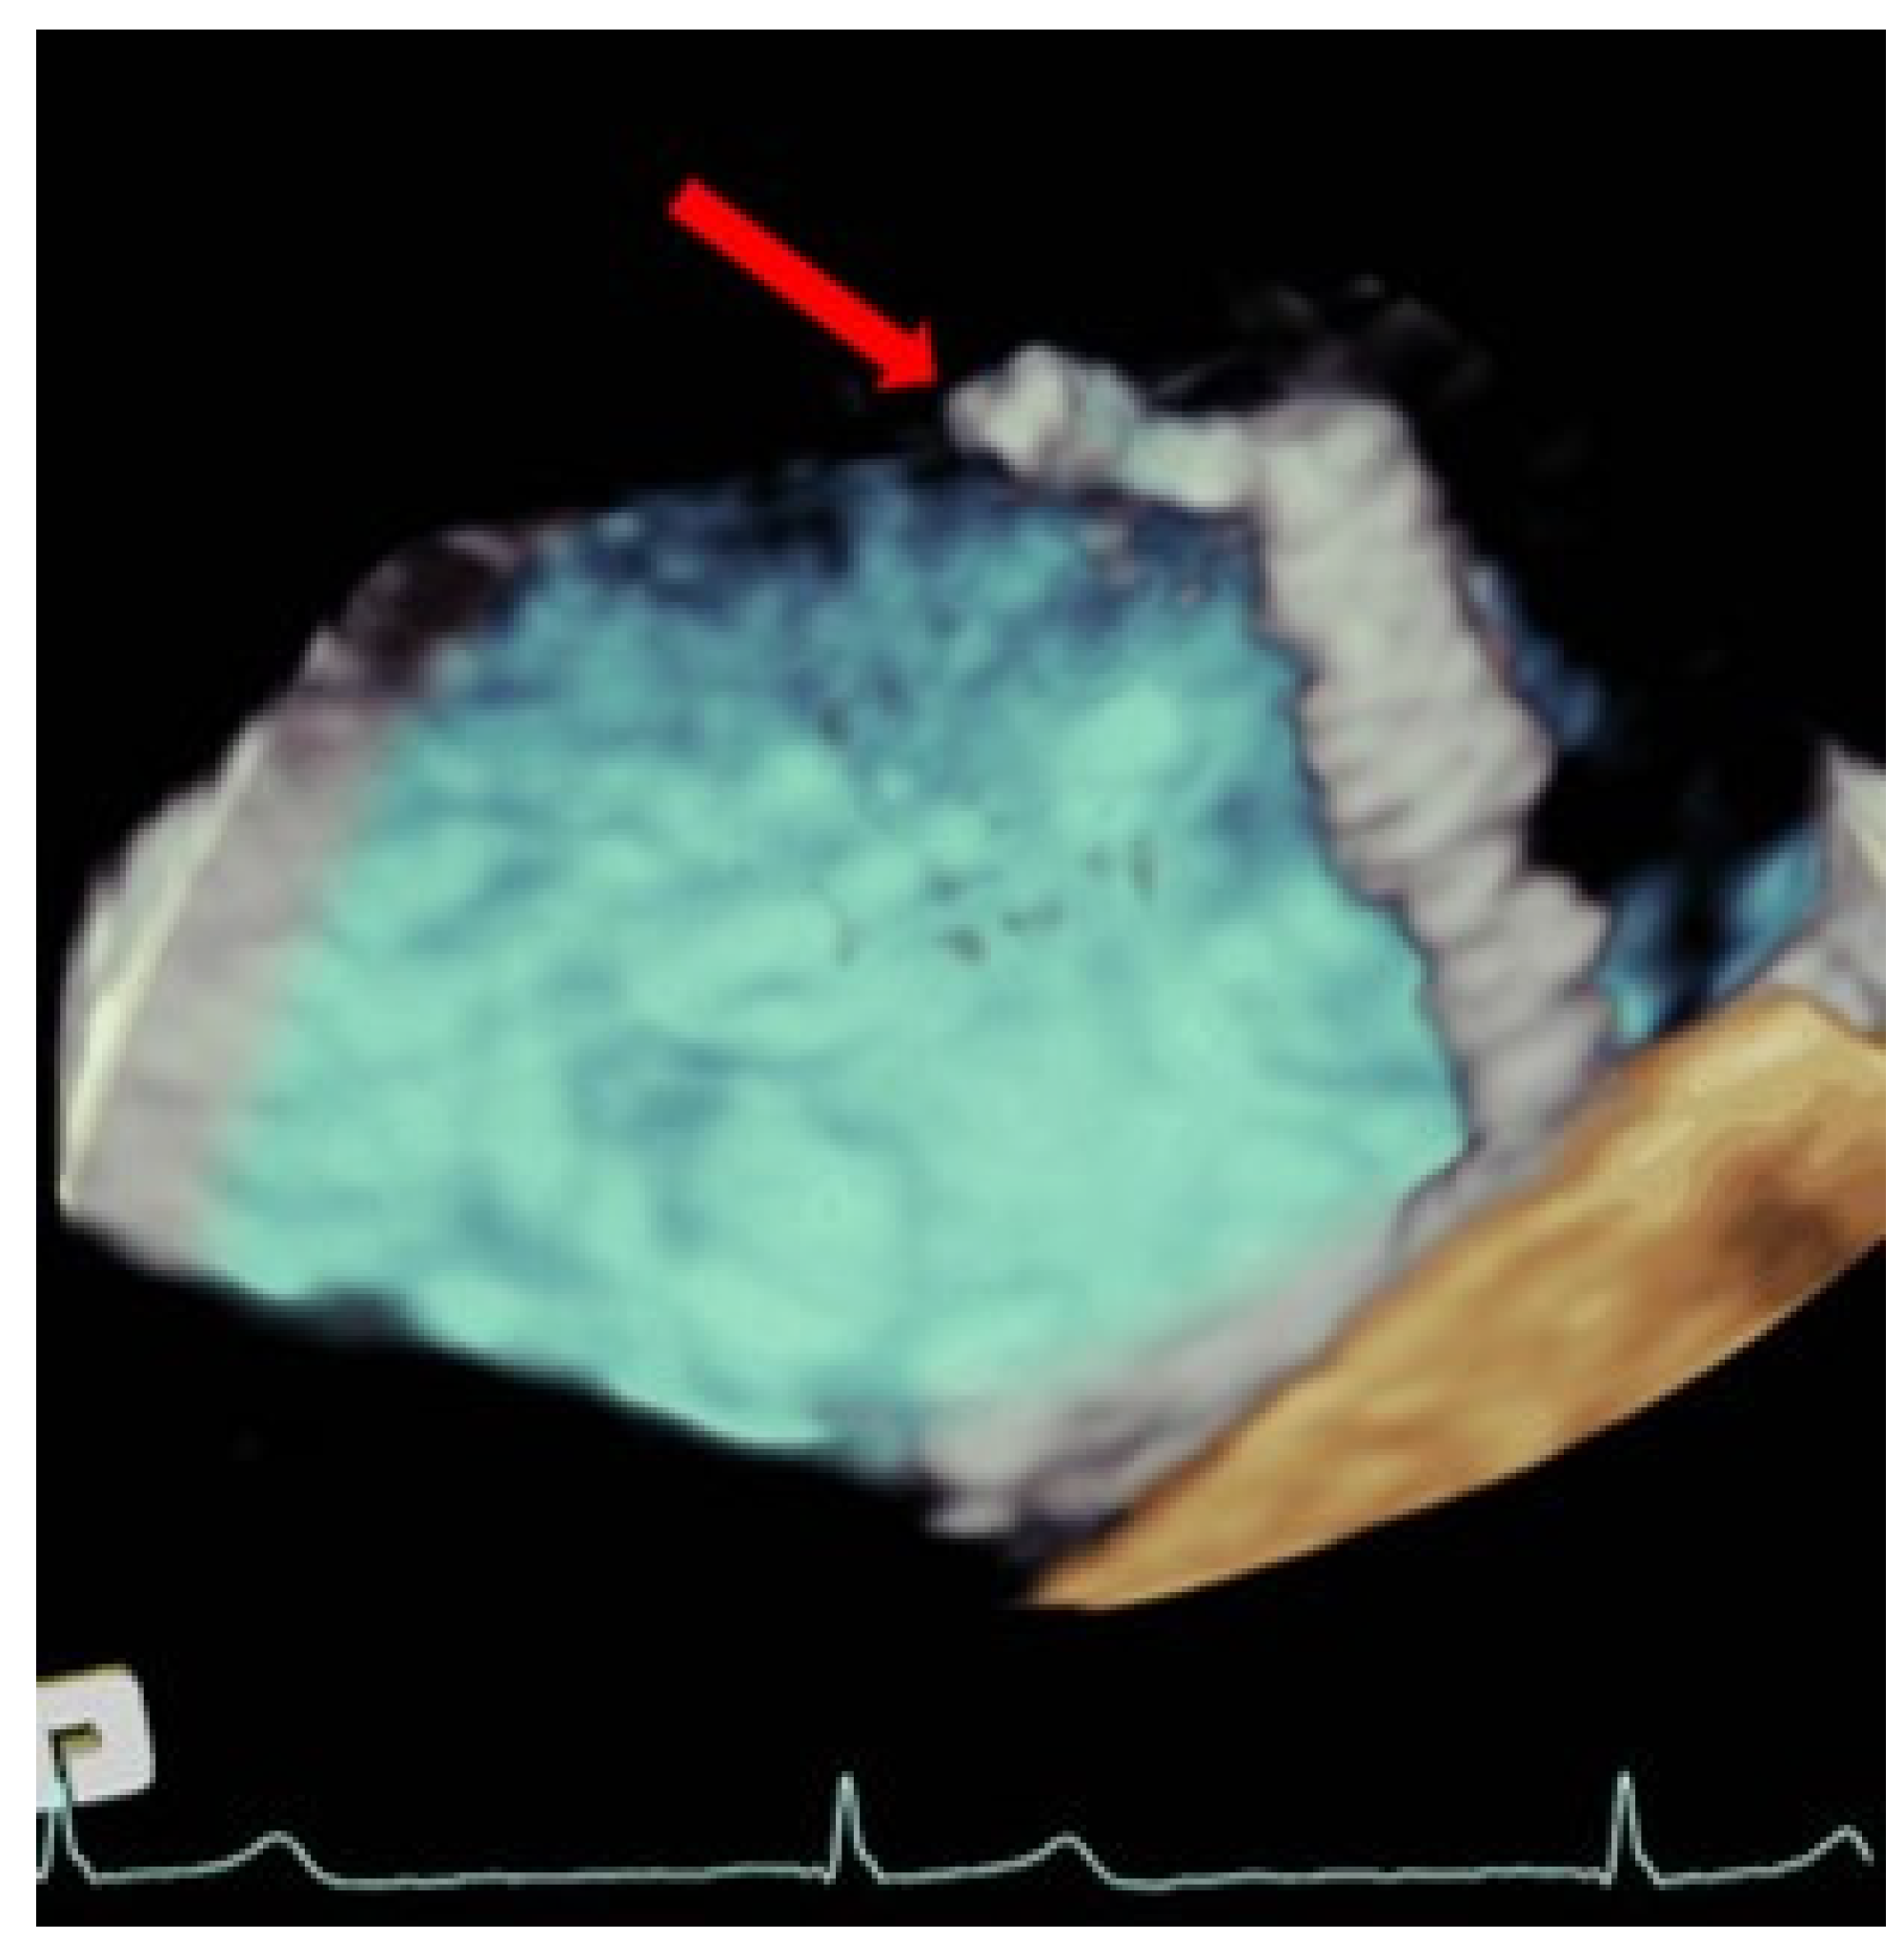

Figure 2.

Three-dimensional transesophageal echocardiogram TEE image showing a large thrombus (red arrow) at the tip of the clip that is emerging from the delivery catheter within the left atrium.